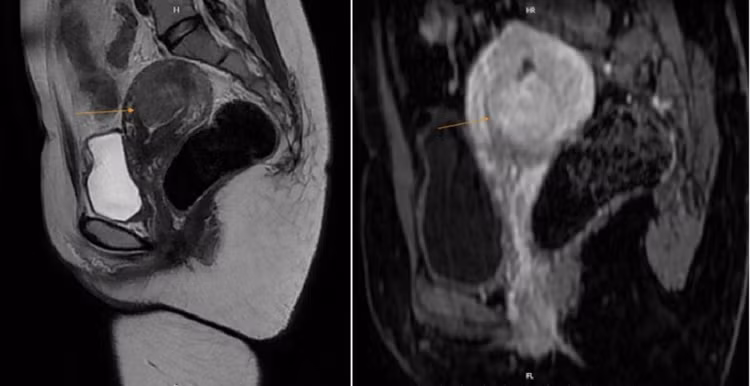

MRI phát hiện một khối u ở trong buồng tử cung của bệnh nhân. Ảnh BVCC

Sau khi khám lâm sàng và siêu âm đầu dò, bác sĩ nghi ngờ chị mắc u xơ tử cung dưới niêm mạc. Kết quả chụp MRI cho thấy khối u lớn trong buồng tử cung, không xâm lấn phá huỷ mô xung quanh. Bệnh nhân được phẫu thuật nội soi và giải phẫu bệnh xác định là u xơ dưới niêm mạc tử cung.